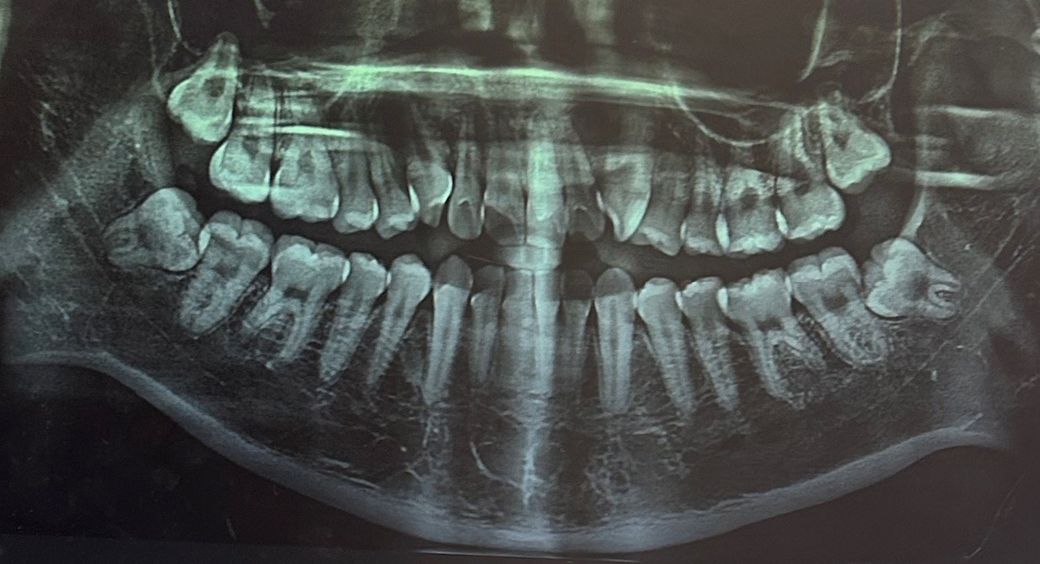

파노라마 사진은 2차원이기 때문에 정확히 신경관과 사랑니 사이 위치 관계를 파악하긴 어렵습니다. 신경관과 근접하여 사랑니가 위치하고 있다는 것 정도만 알 수 있습니다. 설사 사랑니가 신경관을 누르고 있다해도 그거 때문에 신경통이 생기진 않습니다. 삼차신경통이나 턱관절 질환 등 다른 원인을 찾아봐야 합니다.

사진으로 봤을 경우 사랑니의 문제는 없어 보입니다.

사랑니가 기울어져 있기 때문에 해당 부위의 음식물이 많이 끼면 충치가 생길 수 있습니다. 관리를 잘하는 것이 좋으며 이물질이 자주 낀다면 사랑니를 발치해주는 것이 좋을 수 있습니다.